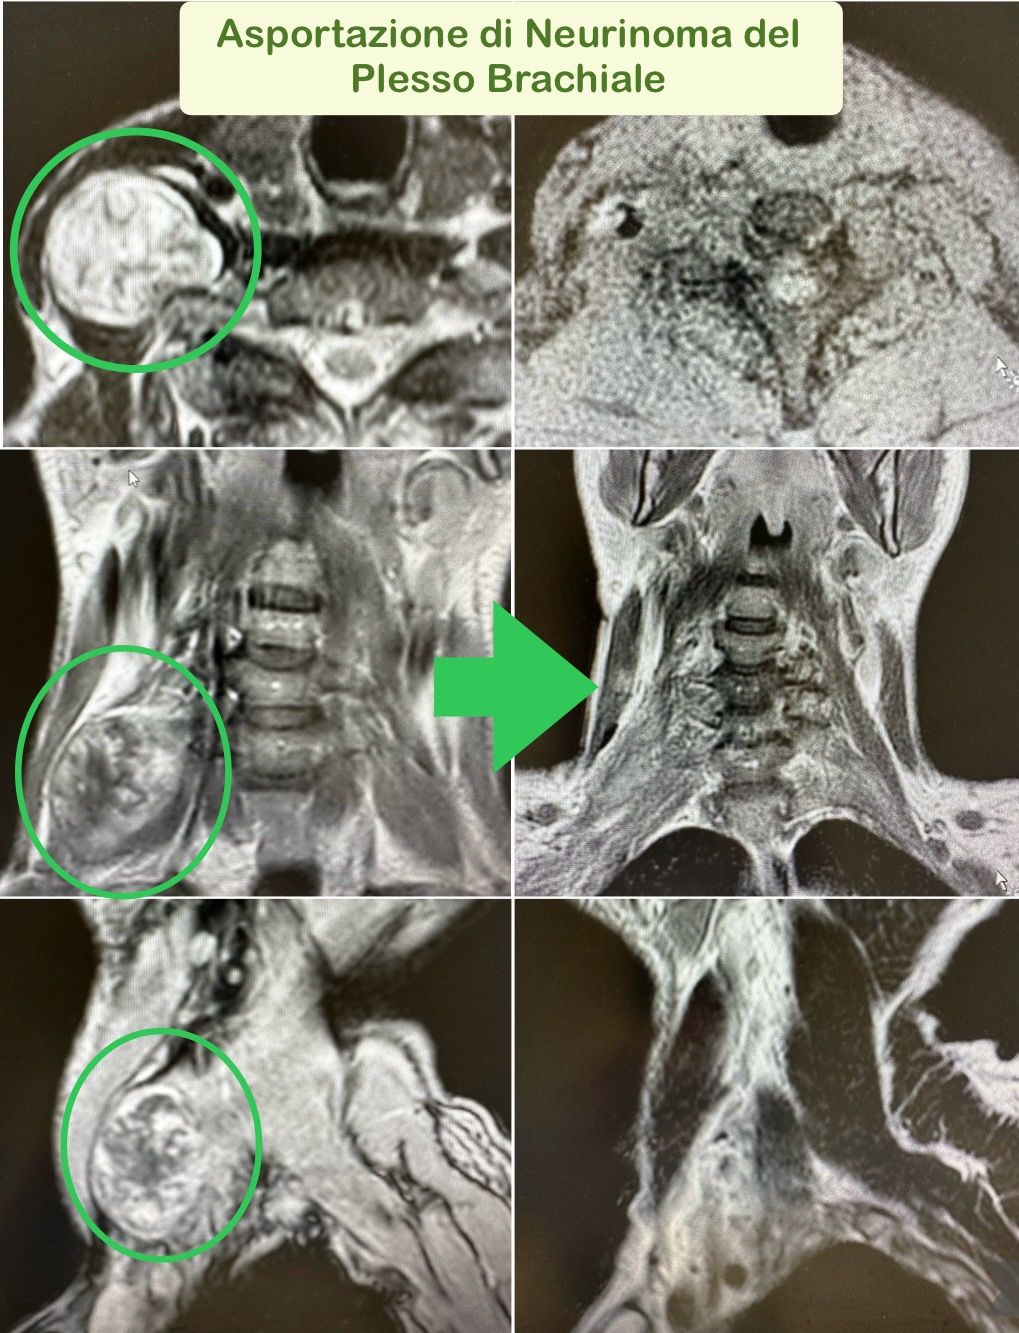

- Microchirurgia dei tumori dei nervi periferici